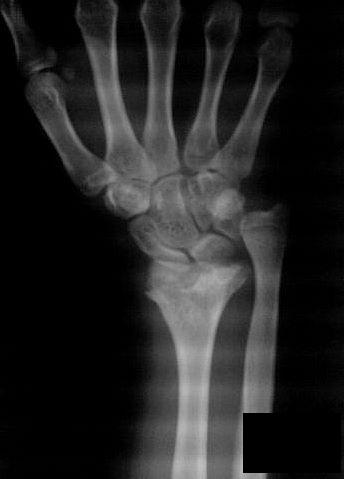

Дисплазия дистальной зоны роста лучевой кости (болезнь Маделунга)

Болезнь Маделунга